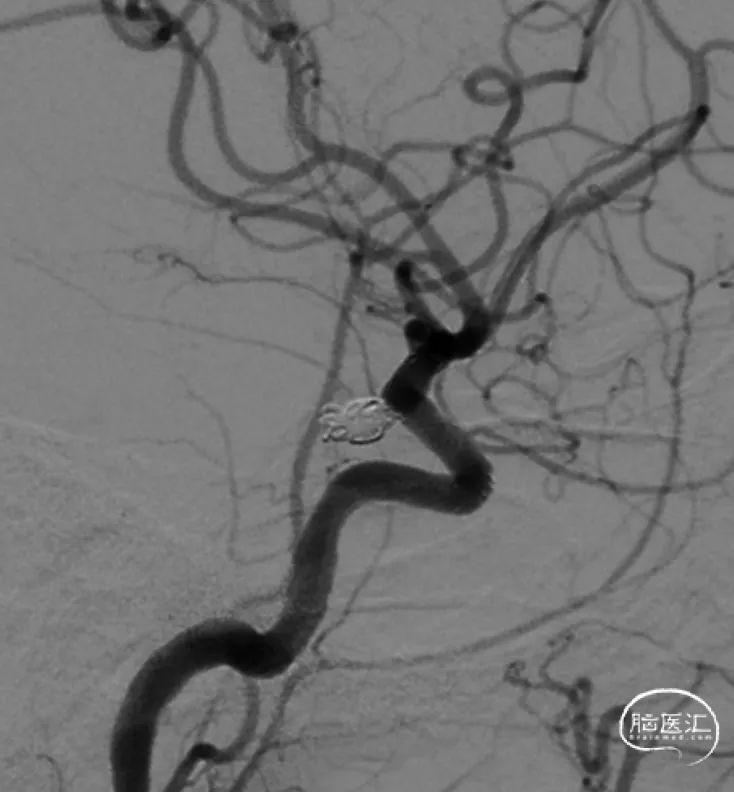

术后影像

➢术后工作位造影

病人术后:动脉瘤已完全栓塞,瘤体不显影,载瘤动脉通畅。